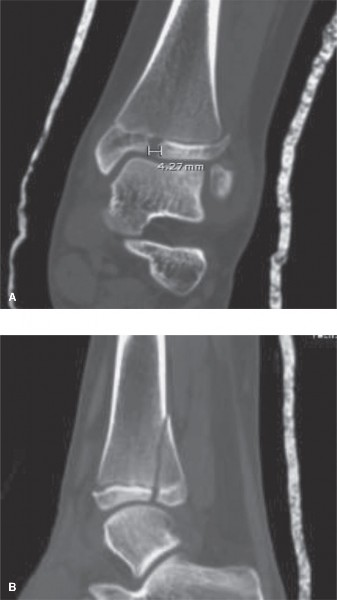

The correct answer is (D). In general, MRI is considered the “gold standard” for evaluation of soft tissue injuries, such as ligaments and tendons. dGEMRIC imaging (as its name implies) is used primarily to evaluate injury to the articular cartilage. CT scanning is generally considered the “gold standard” for evaluation of bony injury and alignment. Because your goal in evaluation post-reduction is assessment of the fracture alignment at the articular surface, a noncontrast CT scan is the best choice. Contrast enhancement in this setting would not add additional useful information. Post-reduction CT images are shown (Fig. 10–16A and B). Based on the images and measurement shown, you recommend (choose the best answer):

Figure 10–16 A–B

The correct answer is (E). In general, >2 mm of residual articular diastasis on radiographs is considered an indication for surgical intervention in an attempt to minimize abnormal joint contact forces and the resultant joint degeneration that occurs over time. This patient has >4 mm of residual articular gap measured on CT scan and is therefore a candidate for surgery. While surgical approaches to treatment of triplane fractures vary, one traditional approach is to reduce the articular surface (either open or percutaneously) and fix it in place using all-epiphyseal lag screws (with or without washers) placed perpendicular to the fracture line in an extraphyseal and extra-articular fashion. Depending on the size of the metaphyseal fragment, additional fixation with lag screws placed across the metaphyseal spike may optimize fracture fixation. This patient has a large metaphyseal fragment and would likely benefit from lag screw fixation in both the epiphyseal and metaphyseal fragments. Compression plating across a growth plate is not typically indicated.